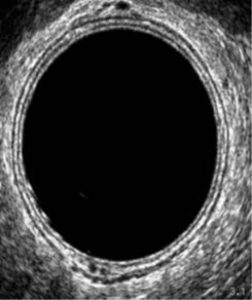

Figura 2. Ampliação da figura 1

Neste exame de ultrassom é adquirido um cubo onde é possível avaliar a lesão de modo tridimensional e realizar as medidas.